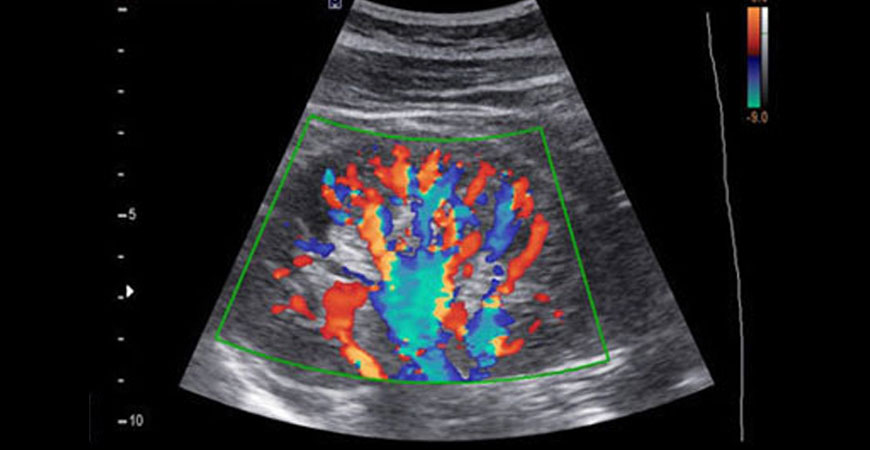

A Doppler ultrasound, also called a Color Doppler test is a non-invasive test that can be used to estimate your blood flow through blood vessels. Our doctors at Aayush Hospital evaluate blood flow through major arteries and veins, such as those of the arms, legs, and neck. It can show blocked or reduced flow of blood through narrow areas in the major arteries of the neck that could cause a stroke.